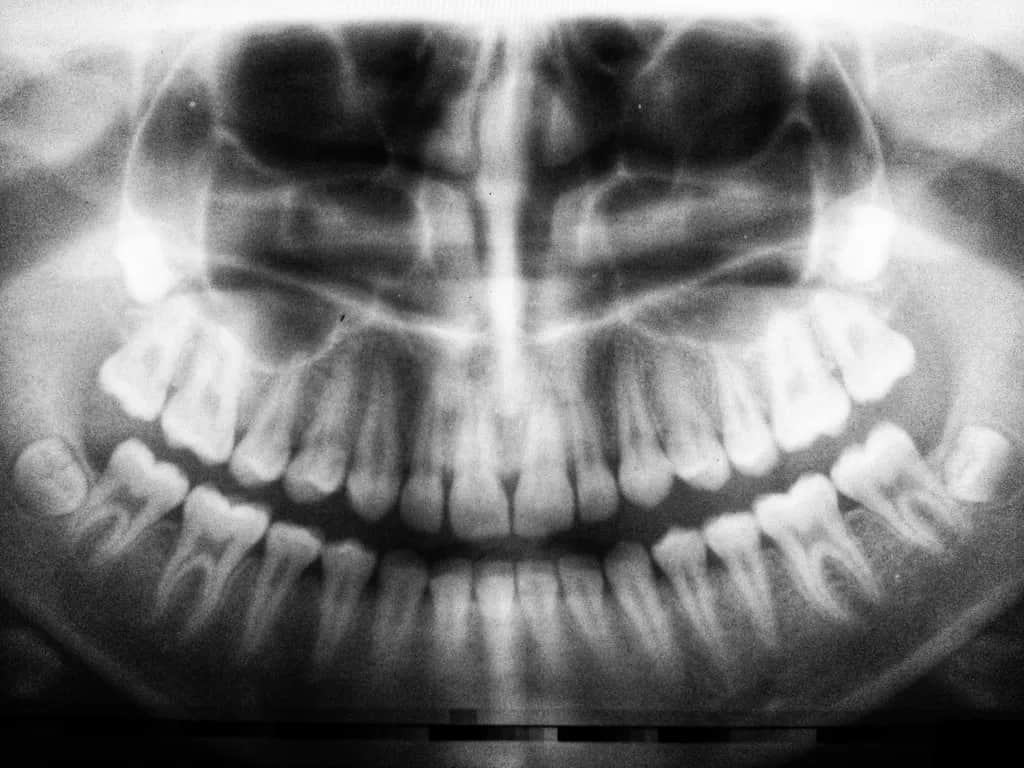

Obrazowanie radiologiczne stanowi nieodłączny element współczesnej diagnostyki stomatologicznej, umożliwiając precyzyjne rozpoznanie schorzeń oraz planowanie skutecznego leczenia. Wykorzystanie promieniowania rentgenowskiego pozwala na uzyskanie szczegółowych zdjęć zarówno pojedynczych zębów, jak i całych struktur szczękowo-twarzowych.